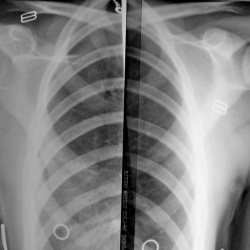

Ребенок 5 лет, из эндокринологического отделения. Анамнез и жалобы смогу узнать только завтра.